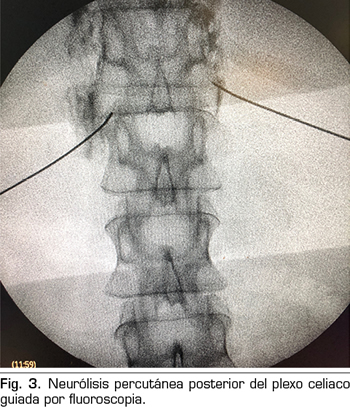

– Abordaje transcrural: el más utilizado para el bloqueo del plexo celiaco (Figura 3). El paciente se coloca en decúbito prono, identificando el cuerpo vertebral L1 y avanzando una aguja por cada lado, a unos 7,5 cm de la línea media, hasta atravesar la crura diafragmática y bloquear el plexo.